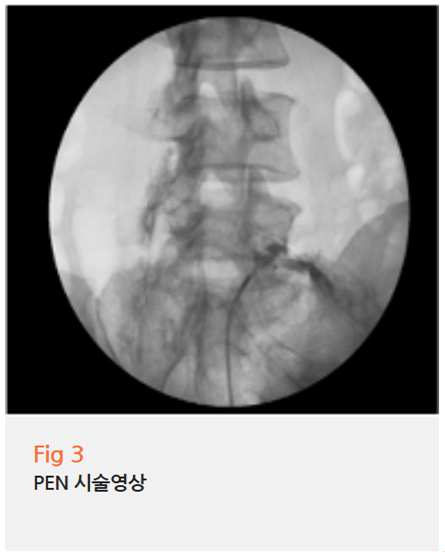

그래서 저는 PEN(Percutaneous epidural Neuroplasty) 시술을 계획했습니다.

PEN 시술은 내시경을 이용해서

직접 신경 압박 부위에 접근하여 유착을 박리하고,

염증을 제거하는 시술인데요.

수술에 비해 부담은 적으면서도, 효과는 확실한 치료법이죠.

그림10.png <병변 부위에 시술하는 장면입니다. ^^ 하단에 기다랗게 보이는 게 카데터예요.>